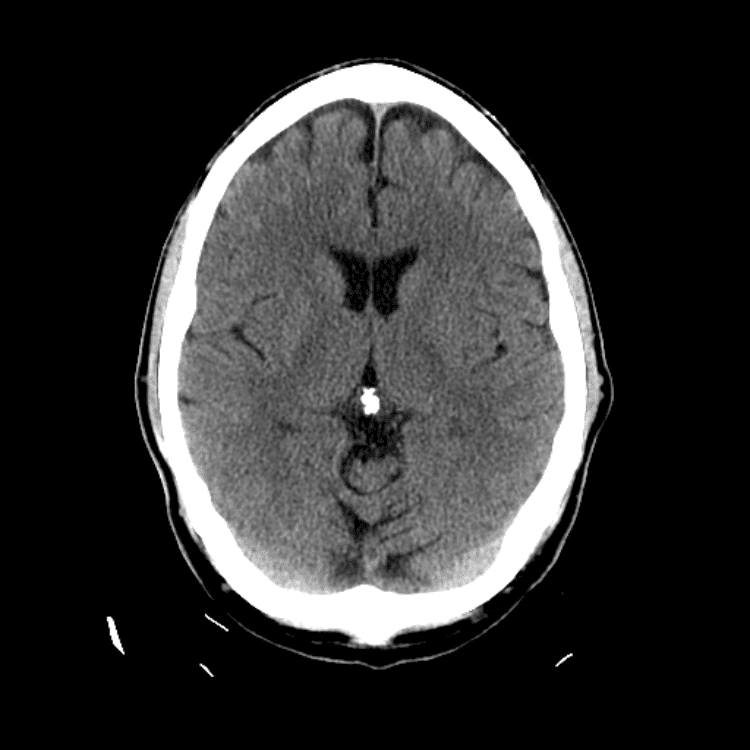

Nontraumatic Brain

Classic